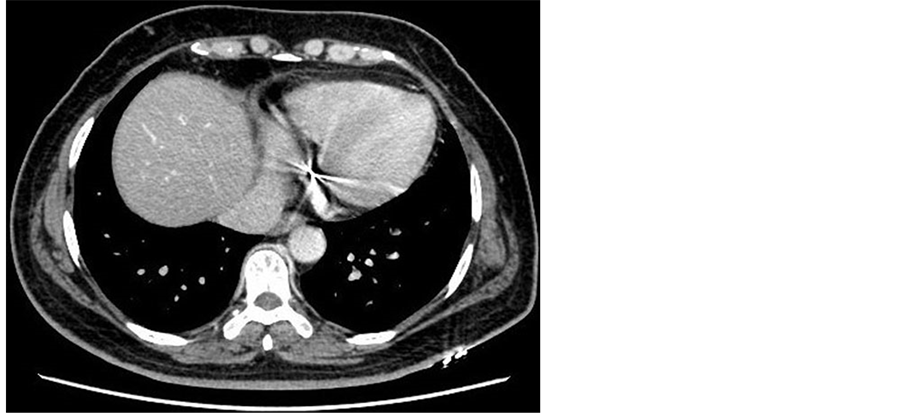

After seven cycles of chemotherapy, enhanced-chest CT (Figure 4) showed the lesions in lung reduced to 4.9 × 3.5 × 3.9 cm. The previous five chemotherapy treatments leaded to a gradual drop of β-HCG from 16,500 mIU/ml to 107.92 mIU/ml. However, the value went up to 151.91 mIU/ml since the latter two cycles of chemotherapy were administrated. Thus, a right pulmonary middle lobectomy was performed. The pathological examination (Figure 5) was also checked and showed a poorly differentiated squamous cell carcinoma of right lung. The auxiliary chemotherapy, regimen of GEM + DDP (Gemcitabine + Cisplatin), was then conducted. After two cycles, we found new lesions in lung CT (Figure 6). The disease progressed because of chemo-resistance. New regimen was initiated with Nedaplatin 130 mg D1 + Etoposide 100 mg D1-5 + Bleomycin 15 mg D1, 3, 5Q3W. Serum β-HCG after each cycle of the chemotherapy, gradually decreased to normal level. The chemotherapy course went successfully. Our 18-month follow-up showed that she had no signs of recurrence.

Figure 4. Computed tomography scan displayed that the mass (white arrow) in the lung had narrowed to 4.9 × 3.5 × 3.9 cm.